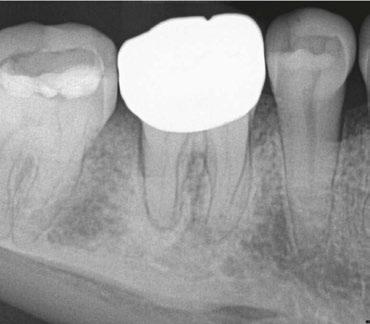

Figure 4 (left): Preoperative image of tooth No. 15. Figure 5 (right): Postoperative image. Rotary negotiation with Roto-reciprocation in all 3 canals with lengths from 25-28 mm and the ProTaper Ultimate Slider advanced to WL within 2 passes

Figure 6 (left): Preoperative image of tooth No. 30. Figure 7 (right): Postoperative image. Rotary negotiation with Roto-reciprocation in all 4 canals and the ProTaper Ultimate Slider advanced to WL within 2 passes without the use of a hand file